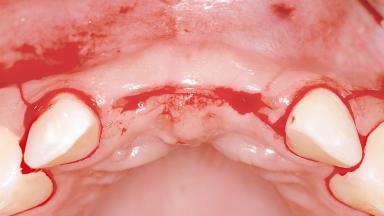

Replacement of Two Central Incisors with Non-Splinted Crowns on Bone-Level Implants

A 27-year-old female patient was referred to the Clinic of Oral Surgery and Stomatology of the University of Bern due to acute pain in the region of her two maxillary central incisors. The patient was in good general health. She reported a bicycle accident approximately 5 years earlier in which teeth 11 and 21 had been traumatized but neither fractured nor displaced. Several weeks after the accident, endodontic treatment was performed on both central incisors, although the patient did not recall the precise reasons for this decision. About 2 years ago, non-vital bleaching had been conducted, in accordance with the “walking-bleach” principle, due to progressive discoloration of teeth 11 and 21.